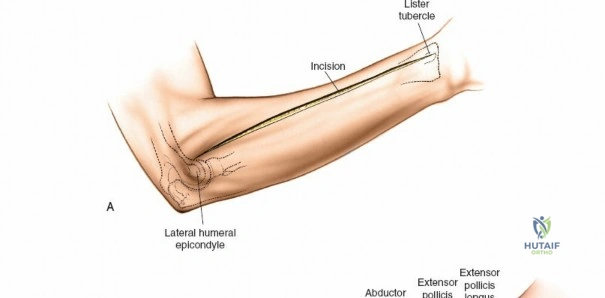

Landmarks and Incision Planning

Accurate identification of surface landmarks is the first step in a successful Henry approach. Palpate the biceps tendon, a stout, taut structure crossing the anterior elbow joint just medial to the brachioradialis muscle. Next, palpate the brachioradialis itself, the fleshy muscle forming the lateral border of the cubital fossa. Finally, identify the styloid process of the radius distally. Note that when the forearm is fully supinated (the anatomic position), the radial styloid is truly lateral.

Make a straight or gently curved incision beginning at the anterior flexor crease of the elbow, just lateral to the biceps tendon. Extend this incision distally toward the styloid process of the radius. The exact length and placement of the incision are dictated by the specific pathology; the approach is highly modular, and often only the proximal, middle, or distal third of the incision is required.

Superficial Surgical Dissection and Internervous Plane